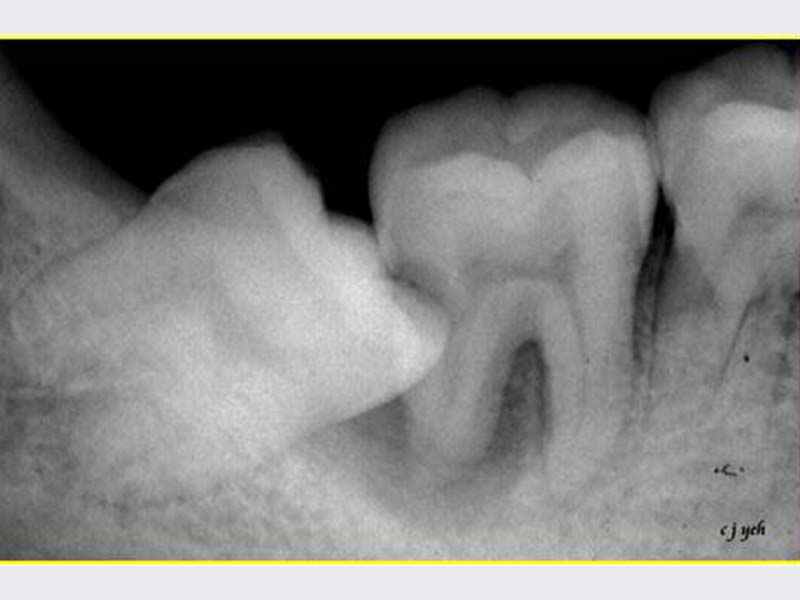

智齒手術

• 智齒手術